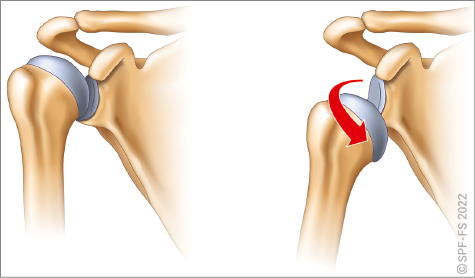

Les membres supérieurs

Les membres supérieurs sont chacun constitués de trois segments :

L'épaule, qui comprend, en plus de la tête de l'humérus, la scapula (anciennement omoplate) et la clavicule, est l'articulation qui relie le membre supérieur au tronc. Le coude relie le bras à l'avant-bras, et le poignet l'avant-bras à la main.

La main comporte cinq doigts, numérotés de 1 à 5 de l'extérieur vers l'intérieur et dénommés : pouce, index, majeur, annulaire et auriculaire. Chaque doigt sauf le pouce comporte trois phalanges numérotées de P1 à P3 (P2 sur le pouce), de la paume vers l'ongle. Le poing désigne la main fermée (tous les doigts pliés), et la paume désigne la face antérieure de la main sans les doigts.

Figure 2-12 : le membre supérieur